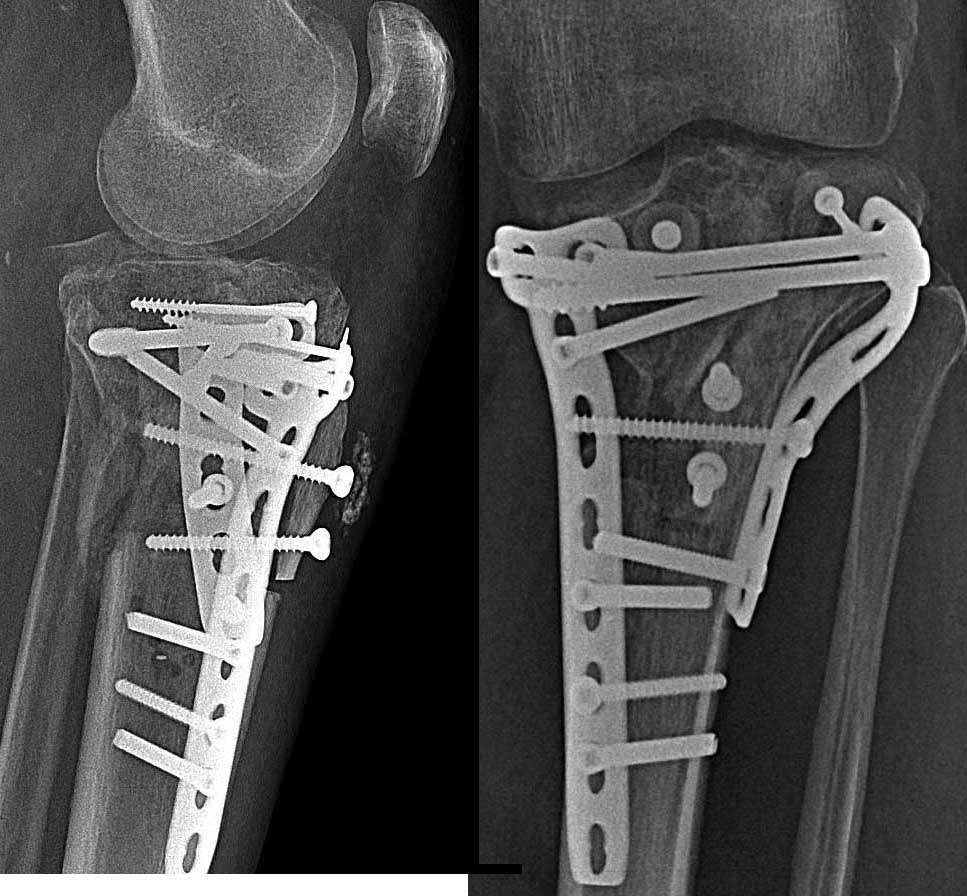

[Ortho] Оскольчатый перелом внутреннего мыщелка + комбинированная нестабильность

через 4 месяца после операции.